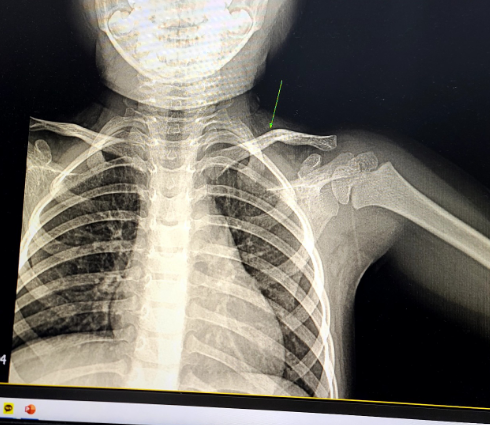

몇 주 전에 여행을 하던 도중에 4살 딸아이 쇄골뼈가 골절되는 상황이 발생했는데요.. 처음에는 겉으로 티가 안 나서 별문제 없나 보다 생각을 했는데 혹시 몰라서 응급실에 가 엑스레이 촬영을 했더니 뼈가 휘어있다고 하더라고요..

아이들은 뼈가 부러지기보다는 뼈가 말랑말랑하여 뼈가 휘기도 한다고 하네요.. 미세하게 금이가고 더 사용하게 되면 똑하고 부러질 수 있는 상황이 생긴다고..ㅜㅜ

- 2주간 2~3일에 병원방문하여 엑스레이 촬영

첫날에 병원에 가고, 2~3일에 한 번씩 병원에 가서 엑스레이를 찍고, 뼈가 붙고 있는지 확인.(뼈가 붙을 때 진액? 이 나온다고 함)